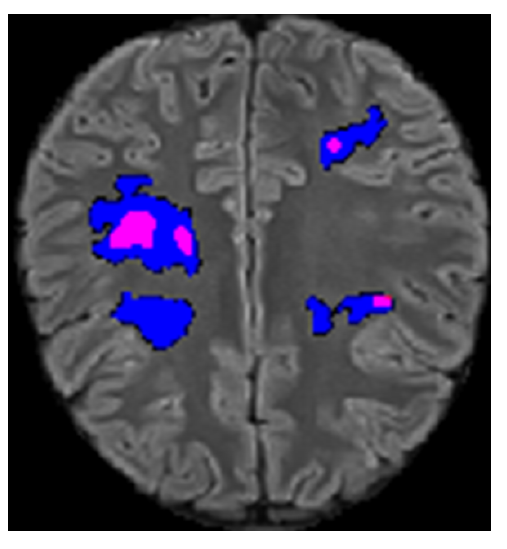

Demyelinating disorders of the central nervous system may have multiple causes, the most common are infections, autoimmune responses, genetic or vascular etiology. Demyelination lesions are characterized by areas were the myelin sheath of the nerve fibers are broken or destroyed. Among autoimmune disorders, Multiple Sclerosis (MS) is the most well-known Among these disorders, Multiple Sclerosis (MS) is the most well-known and aggressive form. Acute Disseminated Encephalomyelitis (ADEM) is another type of demyelinating disease, typically with a better prognosis. Magnetic Resonance Imaging (MRI) is widely used for diagnosing and monitoring disease progression by detecting lesions. While both adults and children can be affected, there is a significant lack of publicly available datasets for pediatric cases and demyelinating disorders beyond MS.

This study introduces, for the first time, a publicly available pediatric dataset for demyelinating lesion segmentation. The dataset comprises MRI scans from 13 pediatric patients diagnosed with demyelinating disorders, including 3 with ADEM. In addition to lesion segmentation masks, the dataset includes extensive patient metadata, such as diagnosis, treatment, personal medical background, and laboratory results. To assess the quality of the dataset and demonstrate its relevance, we evaluate a state-of-the-art lesion segmentation model trained on an existing MS dataset. The results underscore the importance of diverse datasets for developing more robust models capable of handling a broader spectrum of demyelinating disorders beyond MS.